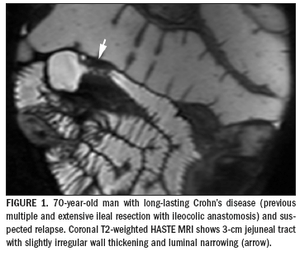

Crohn's disease is an inflammatory disorder ofthe gastrointestinal tract that is characterizedby multiform and, as yet, not well-establishedpathogenesis.